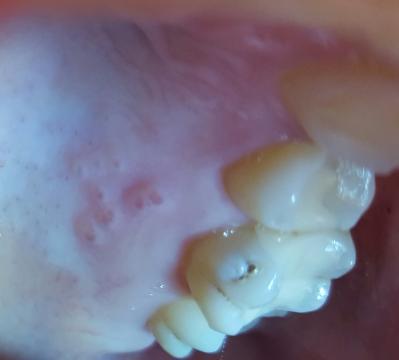

Uz dva dni mam nieco na dasne. Nachadza sa to za zubami z vnutornej strany na dasne v hornej casti. V prvy den som citila len niake vystupky. Nebolelo to. Na druhy den to uz neboli vystupky ale je to zarovno s dasnom ale uz je to citlive na dotyk. Je to pocit ako keby to bolo odrete. Okrem toho ma nic neboli. Na fotke je to ako to vyzeralo v prvy den. Teraz to ma taku farbu do biela.

Dobrý den, vypadá to na slizniční puchýřky, které se mohly udělat v důsledku mechanického dráždění. Zkusila bych vyplachovat ústa odvarem z heřmánku. Pokud se budou tvořit dále, navštivte stomatologa.